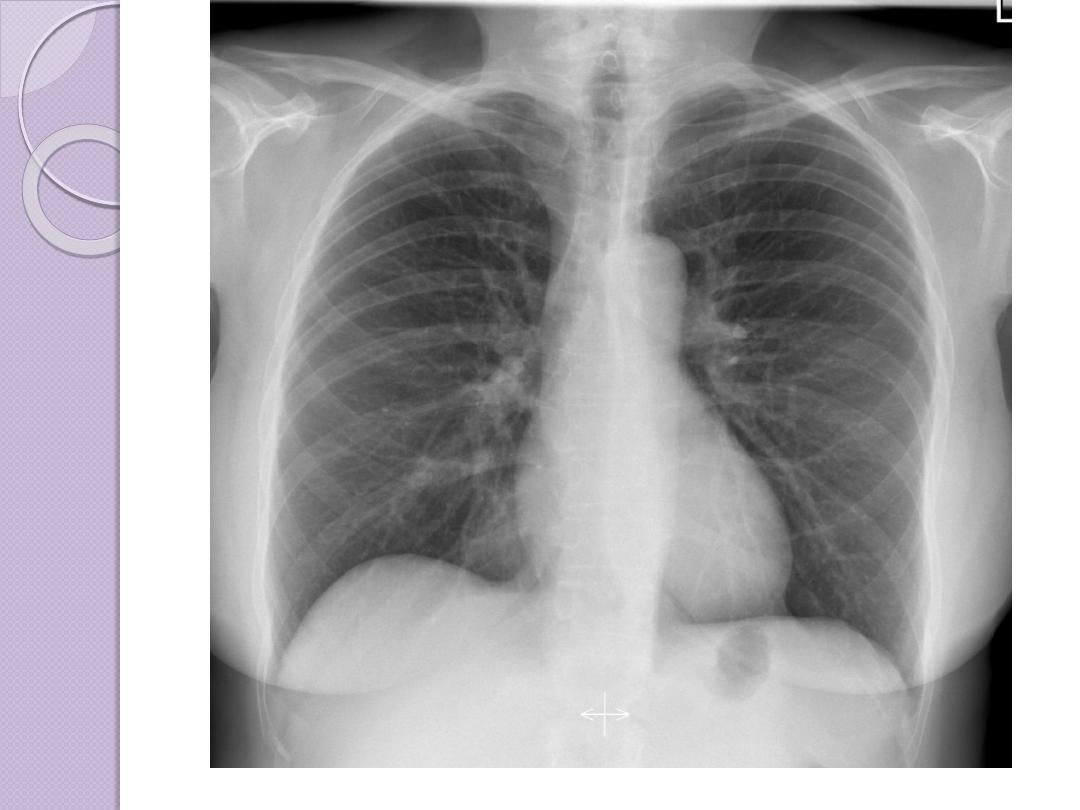

Radiographic Views

Chest and abdominal films are referred to as upright or

supine, depending on the position of the patient. In

addition, chest x-rays are usually described as

posteroanterior (PA) or anteroposterior (AP) or

lateral

These terms indicate the direction in which the x-ray

beam traversed the patient on its way to the detector.

PA means that the x-ray beam entered the posterior

aspect of the patient and exited anteriorly. AP means

that the beam direction through the patient was

anterior to posterior. A left lateral decubitus view is

one taken with the patient’s left side down.

Quiz

name the r

adiographic Views below: